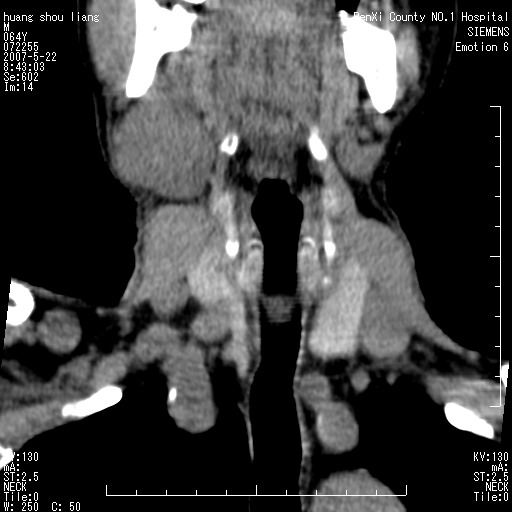

男性,64岁。颈部包块8年。最近增大。

对不起大家,可能是片子发太多有点乱,正常腮腺在下颌角的外侧,颌下腺在下颌体的中部内侧,本例在下颌角内侧偏下,和腺体一点关系都没有,从vrt和mpr上可以很明显看出来,再者肿块是好多粘连在一块的,大家在仔细看看,左侧可能也是吧,我还是考虑为肿大的淋巴结融合在一块,但性质??????

右侧腮腺下部均匀软组织密度肿块,外形不规则,与周围组织分界清晰,考虑右侧腮腺混合瘤或多形性腺瘤。

大家好,病理结果出来了,如大家所说,颌下腺混合瘤。

唉,解剖没学好吧,我诊断错了,不过还是有些不理解回去我在多看看书,谢谢大家的参与,以后我还会奉献好的病例。